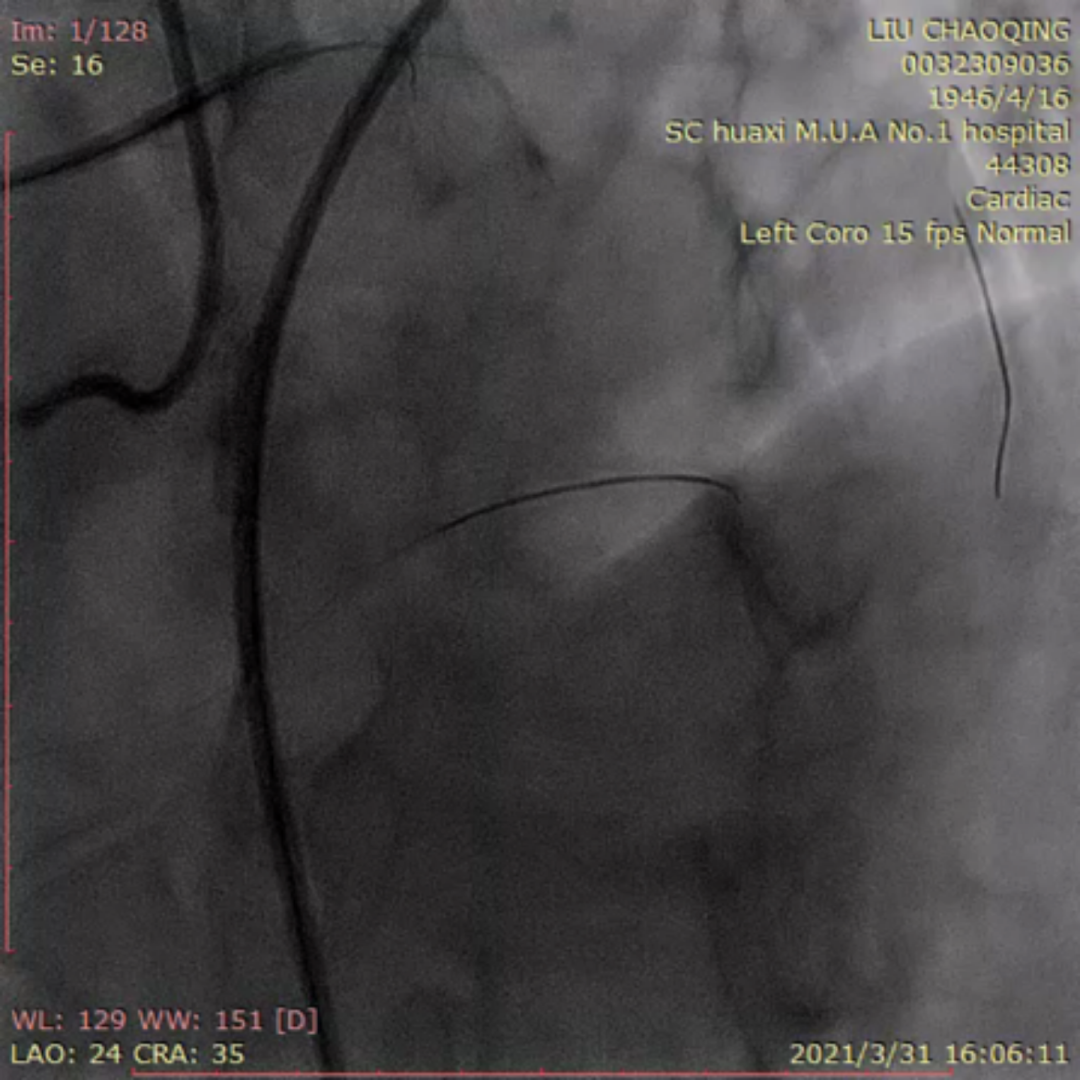

李晨教授:ADR开通前降支CTO一例

来自四川大学华西医院的李晨教授为大家分享了一例ADR开通前降支CTO的疑难病例。患者为老年男性,反复活动后胸痛6月。当地医院冠脉造影提示前降支完全闭塞,尝试PCI未能成功开通血管。予规范药物治疗,患者仍反复有胸痛入院。患者两段CTO,闭塞段长,钙化重,成角,前次失败,J-CTO 4分,右窦上方侧枝供应间隔-前降支;回旋支自身侧枝供应对角支;右冠无明显侧枝;前降支中段着陆区条件较好,ADR着陆区条件尚可。

前降支开口完全闭塞,似见残端

前降支近段可见岛状显影伴钙化

岛状显影处似与对角支相连;但造影剂消散慢,不排除假腔未愈合

前降支中远段可见自身逆向侧枝

右冠远端重度狭窄

右冠窦上方侧枝供应前降支

右窦造影显示侧枝较扭曲

双侧造影:右冠侧枝条件差,自身侧枝供应对角支

患者术中遭遇前降支导丝受阻,对侧和同侧造影前降支远端显影不清的问题。后双侧造影时可见对角支和前降支主支相通。同侧逆向可清晰显示对角支,若进入对角支真腔,可调整方向或通过KDL将导丝放入前降支。随后Pilot 200顺利进入对角支,导丝进入对角支分支。然而随后导丝在第二段闭塞重度钙化处进入假腔,从假腔进入对角支,在远端重回真腔。后启动ADR。最后李晨教授结合病例对逆向及ADR启动时机和ADR穿刺位点选择进行了发表了个人见解。